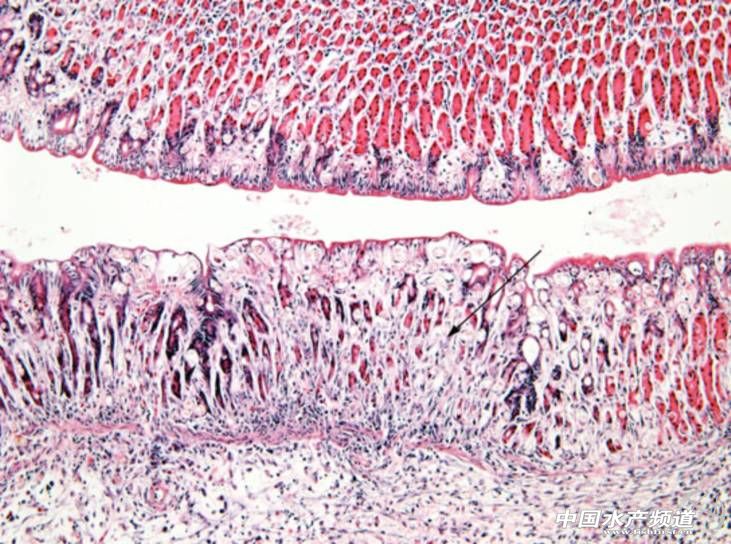

文/廣州利洋水產科技股份有限公司 張吉鵬 中國水產頻道獨家報道,羅非魚是全球主要淡水養殖經濟魚種之一,是動物性蛋白質的主要來源。細菌、病毒、寄生蟲和真菌等都能感染養殖羅非魚,其中病毒病最為棘手,沒有有效的治療方法,主要以預防為主。羅湖病毒是2012年由美國科學家首次發現的危害羅非魚的一種病毒,它是一種新型的RNA病毒,由10個獨特的基因片段組成,直徑55-75nm,目前仍未確定其分類地位,極有可能是正粘病毒科的一種新型病毒,與我們熟知的流感病毒同屬一科。羅湖病毒在24-33℃均可以生長,最適溫度25℃,所以每年的5-10月份均可能導致發病。雖然目前我國未有羅湖病毒感染的病例報道,但作為羅非魚養殖世界第一大國,我們應密切關注羅湖病毒的情況,做好檢測工作。下面根據國外報道的羅湖病毒病的情況,總結一下發病的主要癥狀、流行情況,供大家參考價。 以色列的發病報道 2009年的夏天,以色列的某個養殖場出現羅非魚大量死亡的現象(圖1),規格大小不一,發病時間從5月持續到10月,能夠從一個池塘傳播到另外相近的池塘,傳染性強,發病率達到80%以上。池塘中混養多種魚類,如鯉魚、鯔魚等,但僅有羅非魚發病。同年,自然生長的野生羅非魚也同樣出現大量死亡。病魚體色發黑,體表有潰爛(圖2),眼睛有明顯的病變。發病前期晶狀體渾濁,到后期,晶狀體破裂發炎,眼睛內容物濃縮(圖3),失去正常功能。病理切片顯示腦組織水腫,腦膜局部出血,灰白質充血(圖4),膠質細胞增生,有的血管周圍淋巴細胞淤積(圖5),神經元呈現不同程度的變性;脾臟、腎臟中度淤血(圖6),肝臟和脾臟中黑色素巨噬細胞中心增生。黑色素巨噬細胞中心通常出現在慢性感染病后期,是機體對各種病原感染,尤其是病毒感染的一種反應。 圖1 發病后大量死亡的羅非魚 (圖片來源:Eyngor M, Zamostiano R, Tsofack J E K, et al. Identification of a novel RNA virus lethal to tilapia[J]. Journal of clinical microbiology, 2014, 52(12): 4137-4146.) 圖2 病魚體表潰爛 (圖片來源:Eyngor M, Zamostiano R, Tsofack J E K, et al. Identification of a novel RNA virus lethal to tilapia[J]. Journal of clinical microbiology, 2014, 52(12): 4137-4146.) 圖3 病魚眼睛凹陷,失去正常功能 (圖片來源:Eyngor M, Zamostiano R, Tsofack J E K, et al. Identification of a novel RNA virus lethal to tilapia[J]. Journal of clinical microbiology, 2014, 52(12): 4137-4146.) 圖4 大腦灰白質充血 (圖片來源:Eyngor M, Zamostiano R, Tsofack J E K, et al. Identification of a novel RNA virus lethal to tilapia[J]. Journal of clinical microbiology, 2014, 52(12): 4137-4146.) 圖5 血管周圍淋巴細胞淤積 (圖片來源:Eyngor M, Zamostiano R, Tsofack J E K, et al. Identification of a novel RNA virus lethal to tilapia[J]. Journal of clinical microbiology, 2014, 52(12): 4137-4146.) 圖6 腎臟淤血 (圖片來源:Eyngor M, Zamostiano R, Tsofack J E K, et al. Identification of a novel RNA virus lethal to tilapia[J]. Journal of clinical microbiology, 2014, 52(12): 4137-4146.) 厄瓜多爾的發病報道 2011年,厄瓜多爾也出現了養殖羅非魚大量死亡的現象,魚苗從小池塘移至大池塘后4-7天便開始發病,死亡率80%以上。病魚一般比較消瘦,體表發黑,突眼,鰓絲貧血,腹部膨脹有腹水(圖7)。病理切片顯示肝臟和胃腸道為主要病變器官,肝臟壞死、發炎、并出現合胞體(圖8、9);胃腺壞死(圖10),腸腔中形成蛋白管型。雖然此病例中的癥狀與前面病例中的有較大差異,但科學家們也從中檢測到了羅湖病毒,而癥狀不同的原因還需進一步研究。 圖7 病魚眼睛突出,腹部膨脹 (圖片來源:Ferguson H W, Kabuusu R, Beltran S, et al. Syncytial hepatitis of farmed tilapia, Oreochromis niloticus (L.): a case report[J]. Journal of fish diseases, 2014, 37(6): 583-589.) 圖8 肝臟局部壞死 (圖片來源:Ferguson H W, Kabuusu R, Beltran S, et al. Syncytial hepatitis of farmed tilapia, Oreochromis niloticus (L.): a case report[J]. Journal of fish diseases, 2014, 37(6): 583-589.) 圖9 肝臟中出現合胞體 (圖片來源:Ferguson H W, Kabuusu R, Beltran S, et al. Syncytial hepatitis of farmed tilapia, Oreochromis niloticus (L.): a case report[J]. Journal of fish diseases, 2014, 37(6): 583-589.) 圖10 胃腺壞死 (圖片來源:Ferguson H W, Kabuusu R, Beltran S, et al. Syncytial hepatitis of farmed tilapia, Oreochromis niloticus (L.): a case report[J]. Journal of fish diseases, 2014, 37(6): 583-589.) 埃及的發病報道 2015年,一種被稱為“夏季死亡綜合征”的疾病迅速席卷了埃及的羅非魚養殖場,帶來了巨大的經濟損失。在抽樣調查的68家羅非魚養殖場中,發病的有25家,發病率37%,平均死亡率9.2%,最高死亡率15%,總計損失1億美元。發病季節是夏季,水溫達到25℃以上時開始,且發病率高的池塘其放養密度大。大部分發病池塘混養羅非魚與鯔魚,比例17:3,僅有羅非魚發病。病理切片顯示腦組織發炎,膠質細胞增生,血管周圍淋巴細胞輕度聚集;輕度慢性腦膜炎;肝組織呈慢性肝炎,多壞死灶;腎組織中度病變,多壞死灶,腎間質出血(圖11、12、13)。病魚體表淺層出血、發炎、水腫。 圖11 腦組織發炎 (圖片來源:Fathi M, Dickson C, Dickson M, et al. Identification of Tilapia Lake Virus in Egypt in Nile tilapia affected by ‘summer mortality’syndrome[J]. Aquaculture, 2017, 473: 430-432.) 圖12 慢性肝炎,多壞死灶 (圖片來源:Fathi M, Dickson C, Dickson M, et al. Identification of Tilapia Lake Virus in Egypt in Nile tilapia affected by ‘summer mortality’syndrome[J]. Aquaculture, 2017, 473: 430-432.) 圖13 腎間質出血 (圖片來源:Fathi M, Dickson C, Dickson M, et al. Identification of Tilapia Lake Virus in Egypt in Nile tilapia affected by ‘summer mortality’syndrome[J]. Aquaculture, 2017, 473: 430-432.) 【關鍵字】: 水產養殖 |